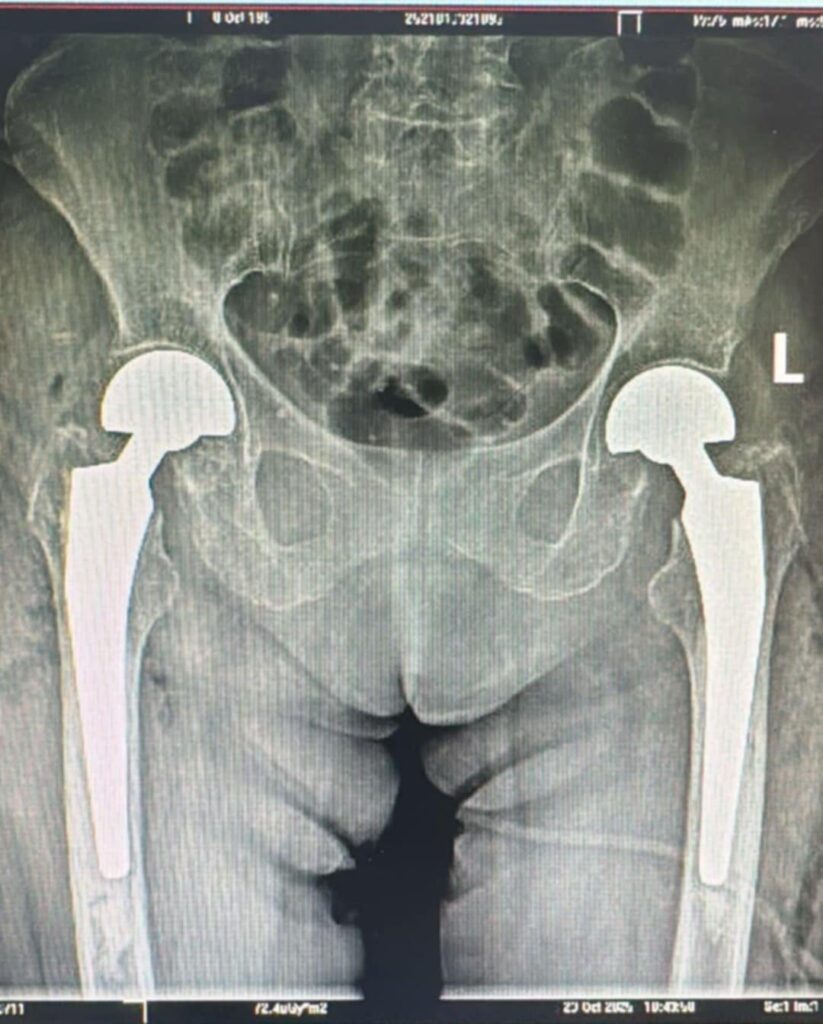

Premieră medicală în județul Sibiu: artroplastie bilaterală de șold realizată într-un singur timp operator, la SCJUS